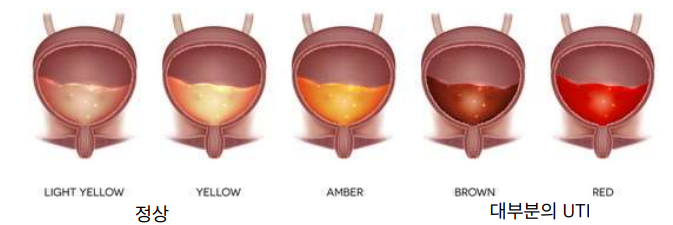

- Typical LUTS (lower urinary tract signs) : stranguria(통증배뇨), hematuria(혈뇨), pollakuira(빈뇨), periuria(이상배뇨; 다른 곳에 소변), dysuria(배뇨통)

| Urinalysis | |

|---|---|

| 물리적 검사 | - 혈뇨 and/or 농뇨 - USG(요비중)의 variation이 큼  |

| 화학적 분석 | - Dip-stick에서 혈뇨, 단백뇨 |